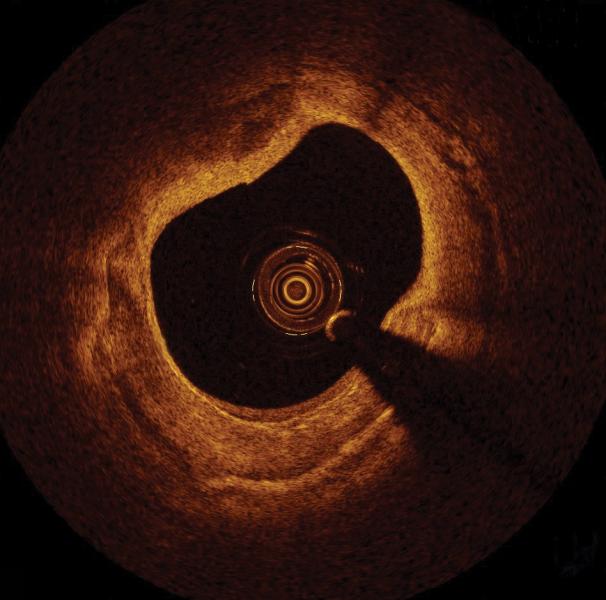

Intravascular imaging is a catheter based system that allows physicians such as interventional cardiologists to acquire images of diseased vessels from inside the artery. Intravascular imaging…